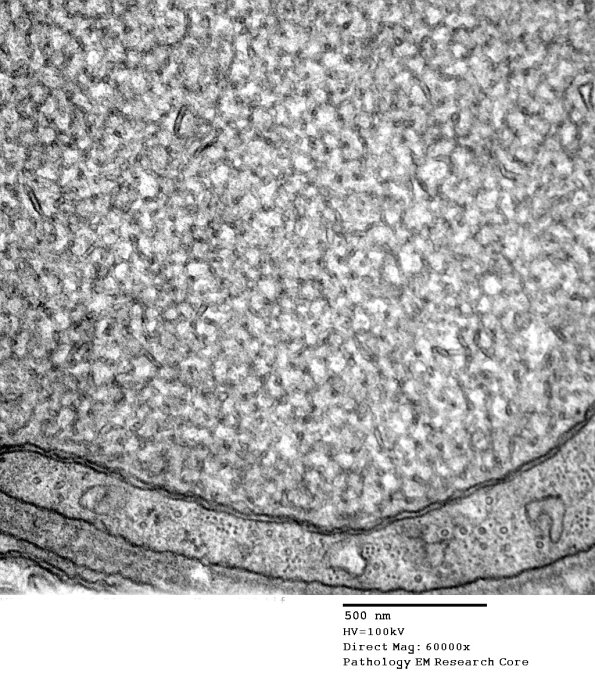

11N2 (Case 18) Nerve_192 - Copy

There must be some commonality linking these cases, perhaps frustrated regeneration. (electron micrographs)